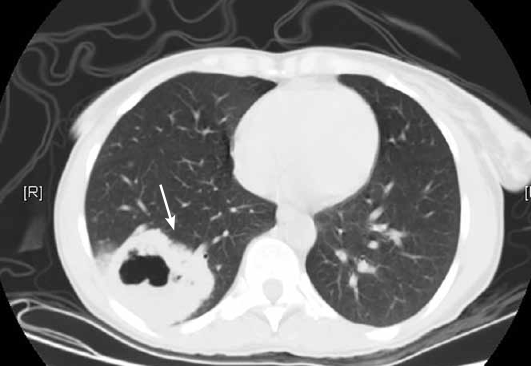

CT scans from these patients, and from a random sampling of 10 percent of the other participants, were visually graded for several cardiovascular findings. The final prediction model included age, gender, CT indication, left anterior descending coronary artery calcifications, mitral valve calcifications, descending aorta calcifications, and cardiac diameter.